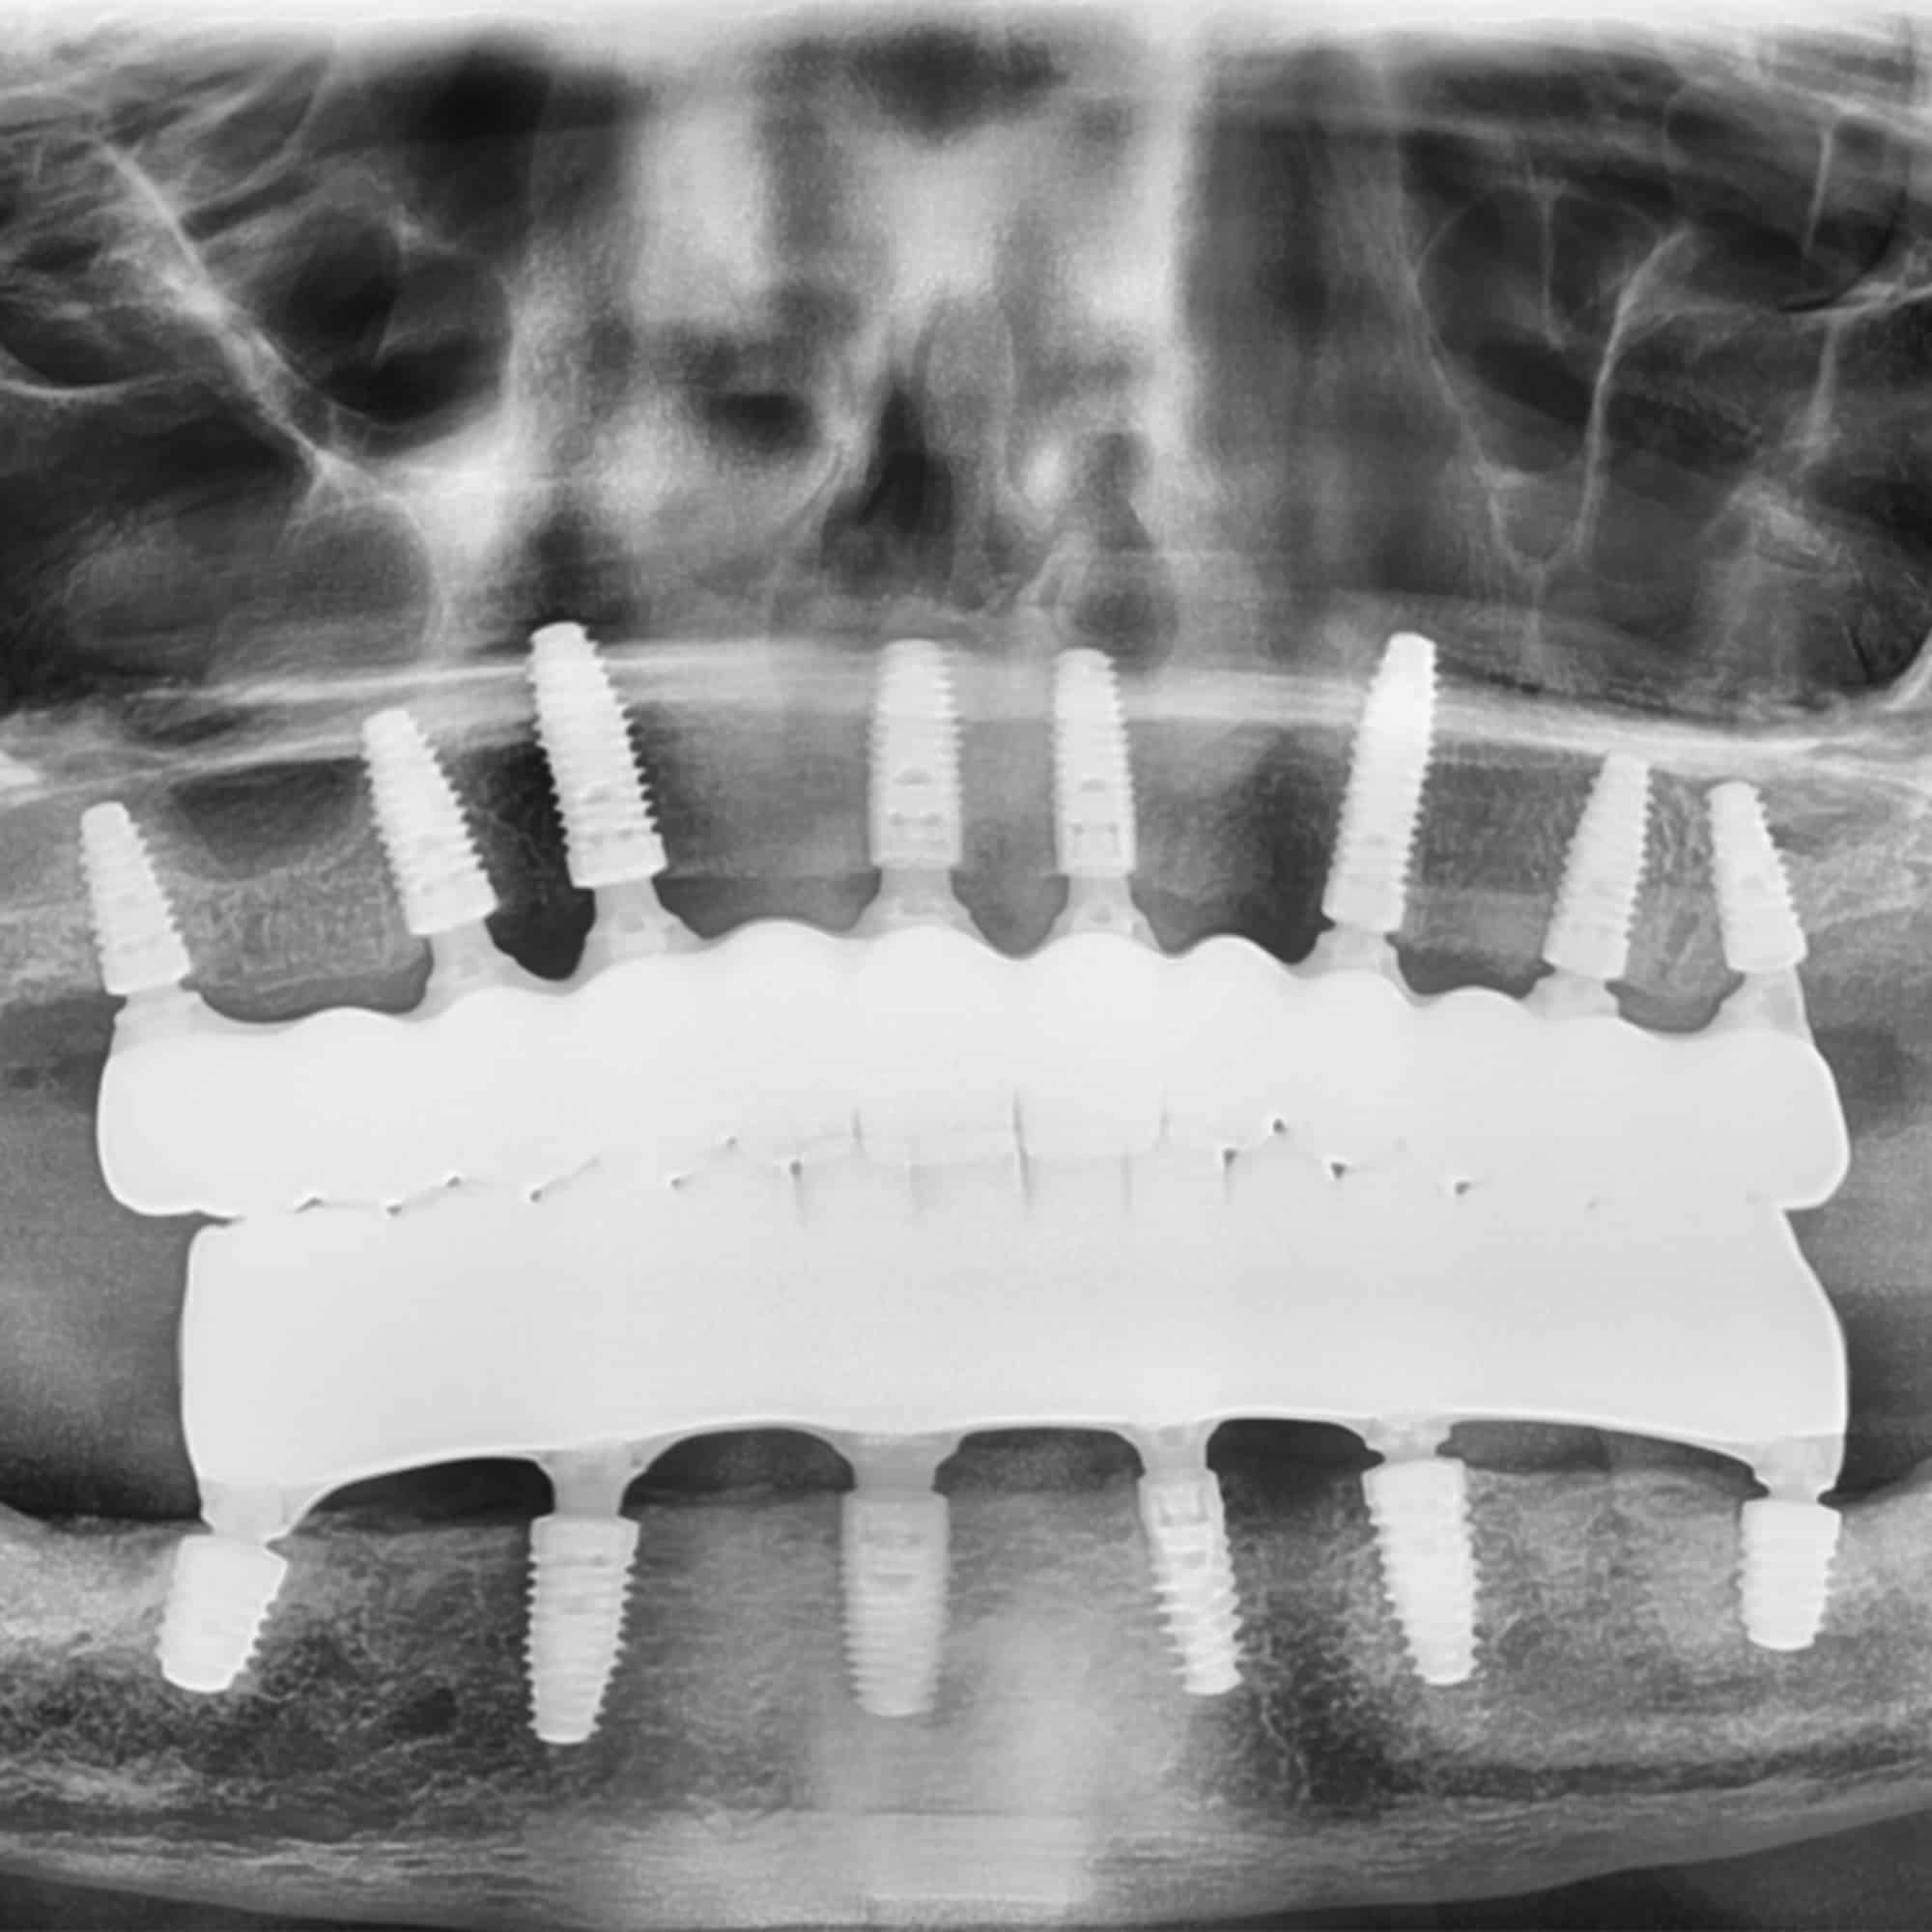

This advanced treatment relies on a series of permanent titanium implants to secure beautiful and natural-looking prosthetic teeth to your upper and lower jawbones.

The Anatomy of Full Mouth Dental Implants

Full mouth dental implants typically include:

- Titanium Implants

Placed by your oral and maxillofacial surgeon in your jawbones, the titanium implants serve as permanent anchors for your prosthesis (artificial teeth) - Abutments

Small connectors that secure the prosthetic teeth to the implants - Prosthetic Arches

Completely realistic, durable sets of teeth custom crafted by a specialized prosthodontist. Arches can be permanently fixed to your implants for convenience or removeable like snap on dentures.

This three-part system creates a foundation that looks natural, feels secure, and stands the test of time.